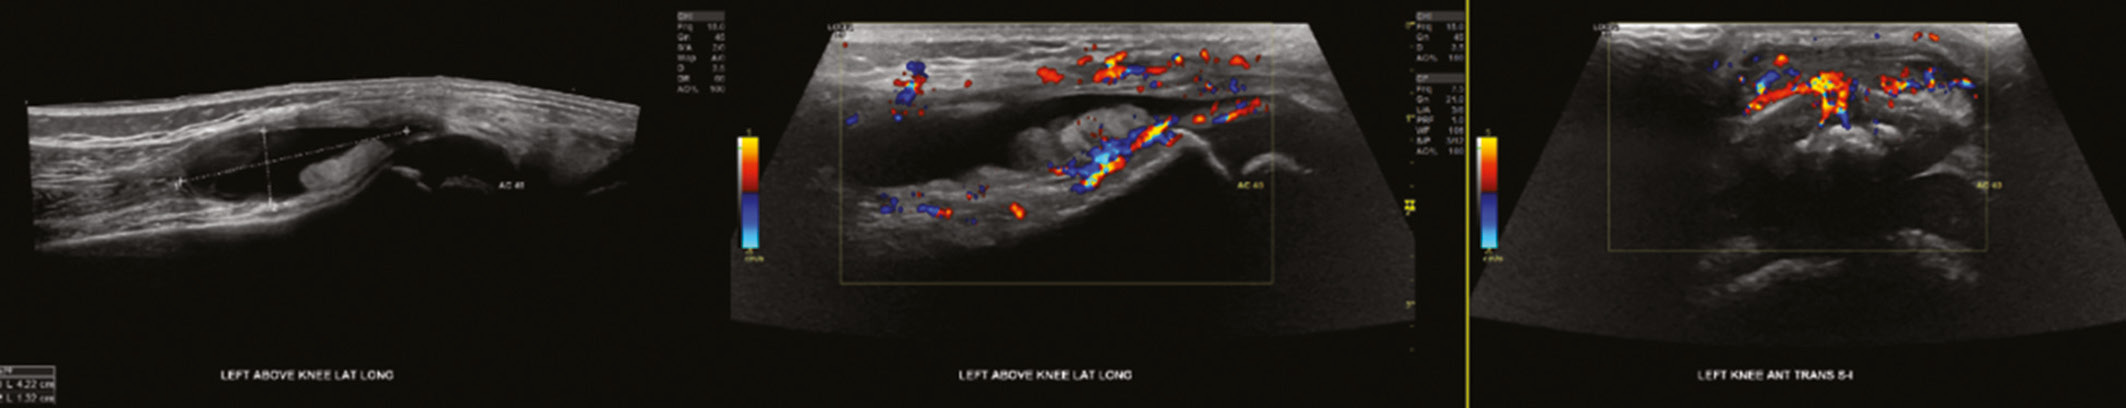

Three days following completion of antibiotics, the patient formally presented to the healthcare system at the ED with his family. He had worsening knee swelling and pain without constitutional signs or symptoms. He localized his pain to his anterior knee just distal to his patella; he could bear weight through the limb but ambulated with a limp. Evaluation of the left knee showed the skin to be without wounds or erythema but with slight warmth compared to the contralateral knee. There was significant prepatellar swelling compared to the contralateral side. There was tenderness to palpation of the prepatellar region but no medial or lateral joint line tenderness. He had pain with terminal flexion but denied pain with axial loading or hip range of motion. He was able to actively extend the knee to 0 degrees and actively flex to approximately 130 degrees. Laboratory evaluation revealed a white blood cell (WBC) count of 10.7, erythrocyte sedimentation rate (ESR) of 36, C-reactive protein (CRP) of 2.6, and negative Lyme test. His left knee radiographs were significant for prepatellar effusion without evidence of a knee effusion (Figure 1). A left knee ultrasound was obtained which showed a 4.2 × 1.3 cm hypoechoic collection suggesting prepatellar bursitis (Figure 2).

Figure 2. Left knee ultrasound showing 4.2 × 1.3 cm hypoechoic prepatellar fluid collection. No significant knee effusion was detected.